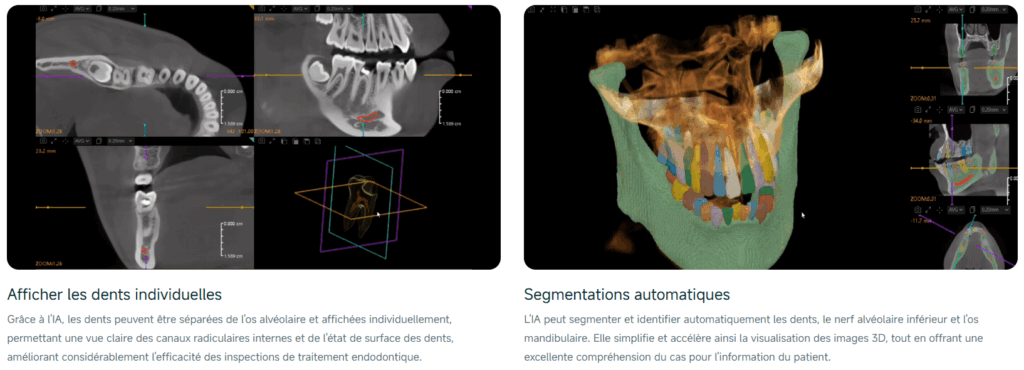

Votre puissant assistant IA